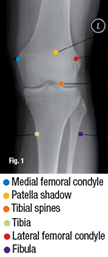

Fig. 1: AP view of the knee.

There are a few common normal variants that are viewed on a knee series that can appear as pathology. A limited series of the knee consists of AP, lateral and sunrise views. The AP view of the knee (Fig. 1) can be performed with the patient either supine or weight-bearing. It can be performed with or without a grid technique. The central ray is angled 5 degrees cephalad and enters at the inferior margin of the patella. The main areas to evaluate are the joint space between the femur and tibia, the integrity of the bones and alignment. The adjacent soft tissues should also be evaluated. There are two common findings that are normal variants: an accentuated groove for the popliteal tendon in the lateral condyle and bipartite patella. AP View